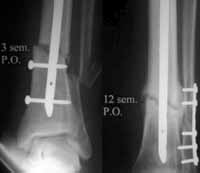

En los pacientes que recibieron clavos no fresados se presentó, además, un caso de retardo en la consolidación y ruptura de un perno de bloqueo proximal, que requirió injertos óseos, lográndose finalmente la consolidación hacia las 20 semanas. Se encontró un caso de ruptura del clavo en una fractura de diáfisis distal que no había consolidado hacia las 14 semanas y que requirió retiro del clavo y osteo- síntesis con placa e injertos óseos, por lo cual fue retirado del estudio posterior a la falla del implante (Figura 4).

Figura 4. Ruptura del material de osteosíntesis secundaria a la no unión de la fractura.